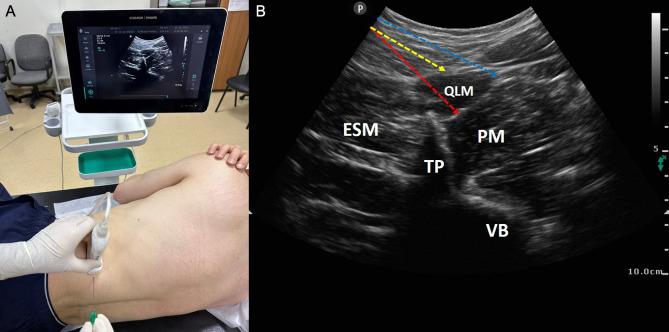

The sine qua non of enhanced recovery after surgery protocols designed to improve the perioperative experiences and outcomes of patients is to determine the most appropriate analgesia management. Although many regional techniques have been tried over the years in this purpose, interfacial plane blocks have become more popular with the introduction of ultrasound technology into daily practice and they have great potential to support effective postoperative pain management in many surgeries. The current article focuses on the benefits, techniques, indications, and complications of interfascial plane blocks applied in cardiac, abdominal, and spine surgeries.

旨在改善患者围手术期体验和结局的术后加速康复方案的关键在于确定最恰当的镇痛管理。尽管多年来为实现这一目的尝试了多种区域技术,但随着超声技术应用于日常实践,界面平面阻滞越来越受欢迎,并且在许多手术中具有支持有效术后疼痛管理的巨大潜力。本文重点关注在心脏、腹部和脊柱手术中应用的筋膜间平面阻滞的益处、技术、适应证及并发症。